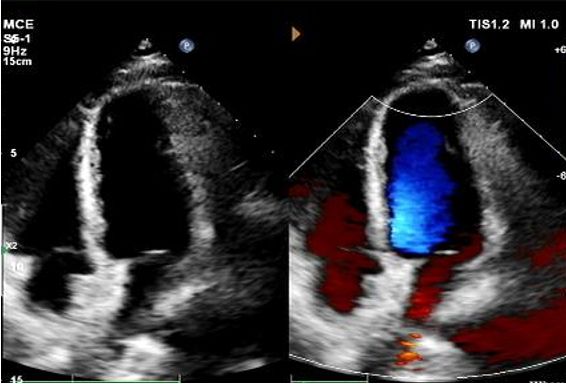

Key Follow-Up Imaging Findings

Day 1 to 9 Months:

No residual shunt observed.

Gradual reduction in device echogenicity.